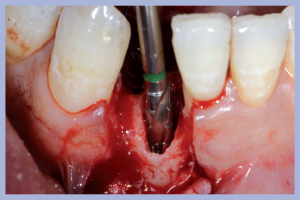

Decidiamo di utilizzare l’alveolo dell’elemento 4.1 modificandolo in fase di perforazione, questo comporta un’inclinazione di perforazione ad emergenza distale. Utilizzando un impianto Leone cilindrico trasformiamo la cavità alveolare residua da tronco-conica a cilindrica. Quanto sopra ci permette di recuperare stabilità primaria al terzo medio e apicale (Fig. 4).

- Fig. 4

- Fig. 4a

- Fig. 4b